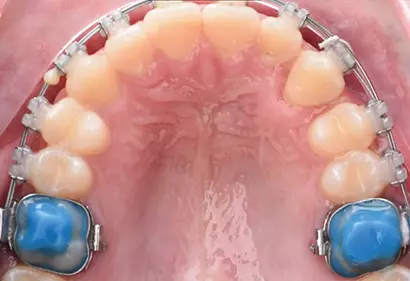

- Брекеты

- Лечение